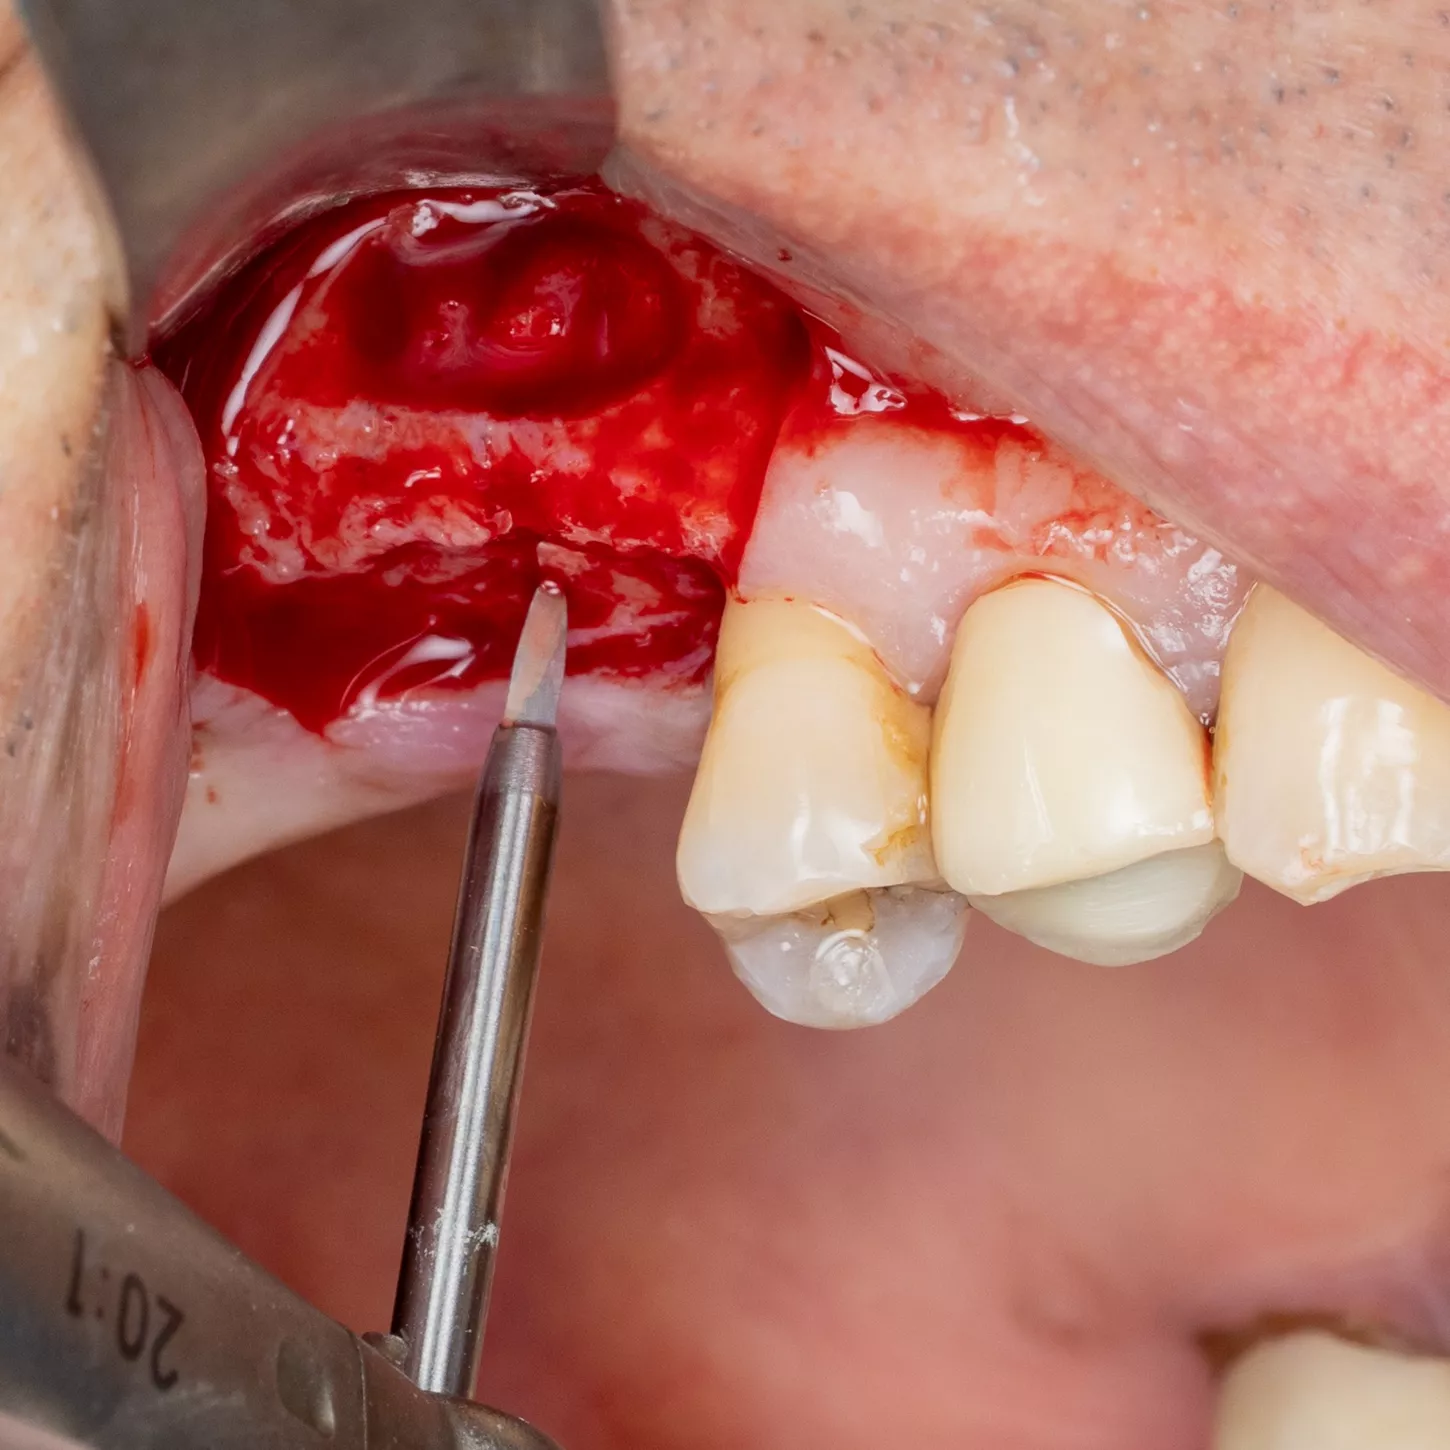

7. Sinus mucosa detached.

8. Verification of the absence of mucosal adherence at the Beta angle and at the inter-sinus-nasal septum using a Freer sinus elevator.